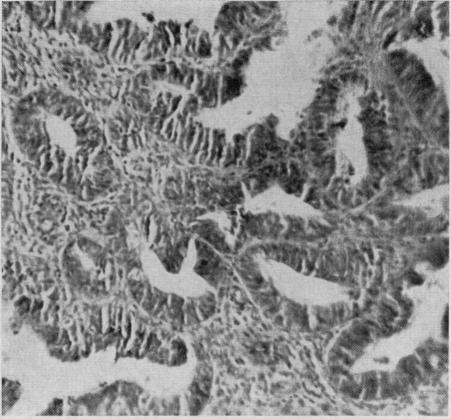

Carcinoma of endometrium and polycystic ovaries in a 22-year-old patient.

Can Med Assoc J. 1967 Jun 3;96(22):1473-6.